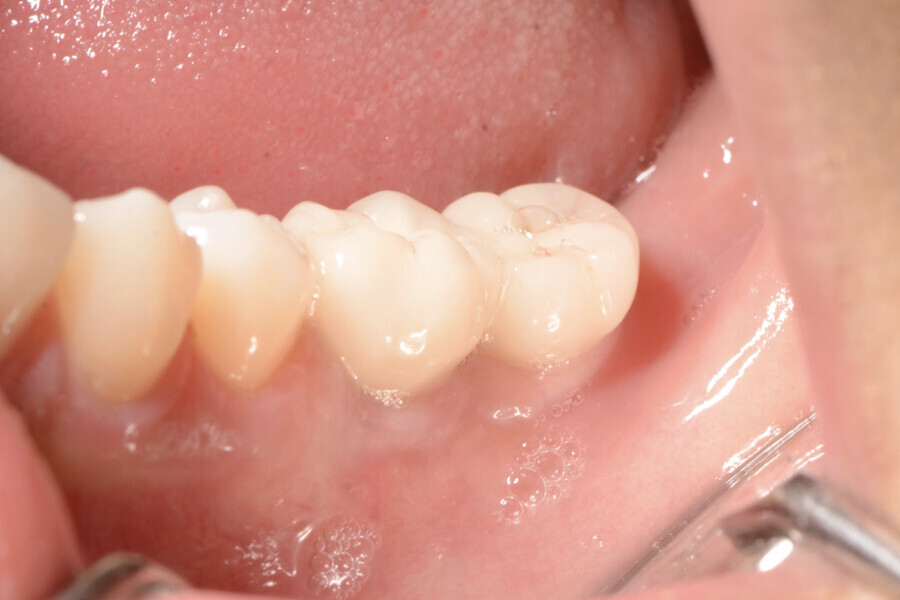

Aspect clinique de la zone des tissus mous péri-implantaires lors du suivi à cinq ans. (Photo : Dr Cosimir Dima)

Dix jours après l’intervention, les sites donneur et receveur étaient parfaitement cicatrisés (Figs. 15 et 16). Des visites de contrôle ont été prévues deux et quatre semaines plus tard, suivies de visites à trois, six et douze mois, puis tous les six mois pendant cinq ans (Figs. 17 à 20).

La profondeur de sondage du site péri-implantaire a été mesurée au niveau du point médian inter-proximal, et la valeur la plus élevée entre le bord des tissus mous et le fond du sulcus péri-implantaire a été retenue. Une lime endodontique ISO n° 15 a été utilisée pour évaluer l’épaisseur de la muqueuse péri-implantaire vestibulaire à 2 mm des bords des tissus mous en mésial, distal et médial de la plate-forme de l’implant (point de référence). La muqueuse kératinisée a été évaluée au début du traitement, puis lors des suivis au moyen d’une sonde parodontale. Les mesures ont été prises verticalement au niveau du point médio-vestibulaire, depuis la plate-forme de l’implant jusqu’au bord libre de la gencive. Elles ont été effectuées en préopératoire, immédiatement après l’intervention, puis à quatre semaines, un an et deux ans par la suite. Les paramètres cliniques (largeur de la muqueuse kératinisée, volume de la muqueuse, et recouvrement de la récession gingivale) ont été enregistrés au début du traitement, et lors de chaque visite de suivi. La largeur initiale de la muqueuse kératinisée était minimale (1 mm). À quatre semaines, le gain de largeur de la muqueuse kératinisée était de 2 mm, puis de 3 mm après un an, et de 4 mm après cinq ans.

À quatre semaines, le gain de volume de la muqueuse était de 3 mm, puis de 4 mm après un an, et de 5 mm après cinq ans. Le recouvrement de la récession était déjà complet après quatre semaines, et l’était toujours après un an et après cinq ans.